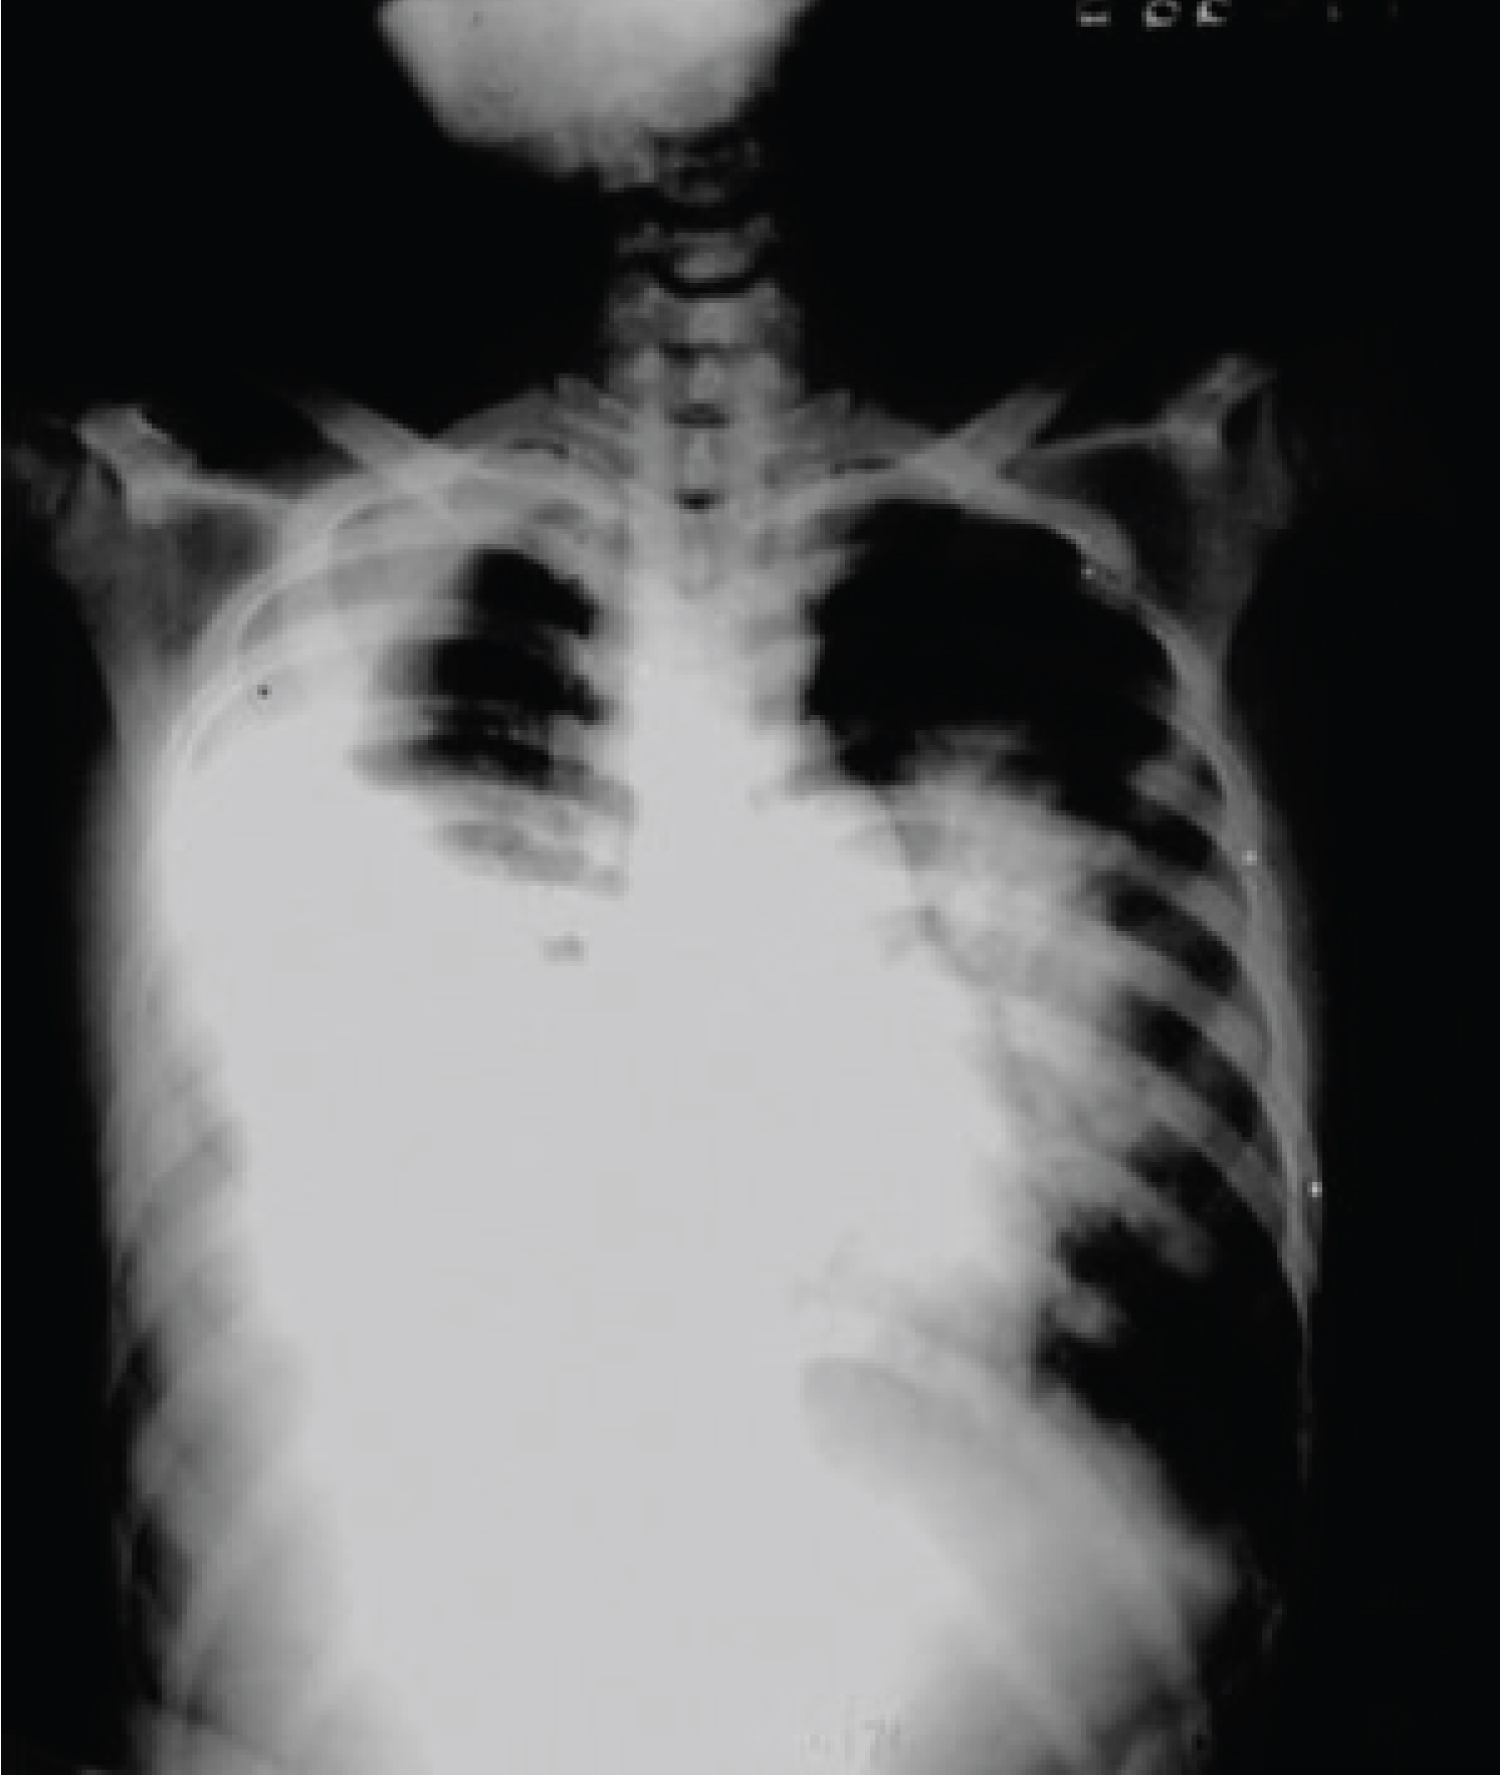

The patient’s admitting chest X-ray showed a large right-sided pleural effusion and an infiltrate involving the right lower lobe (Figure 1). Gram stains of her sputum and pleural fluid revealed numerous neutrophils and slender Gram-negative rods. She was placed on intravenous clindamycin at a dose of 30 mg/kg/24 hours. Shortly after admission her condition suddenly worsened when, while lying on her left side, she aspirated the contents of a large and unsuspected right lung abscess into her left lower lobe (Figure 2). Her condition gradually improved with intensive respiratory therapy including tracheal suctioning and continuous positive airway pressure oxygen administration.

Figure 1: Admitting chest X-ray shows a large right pleural effusion and a pneumonic infiltrate in the right lower lobe. View Figure 1